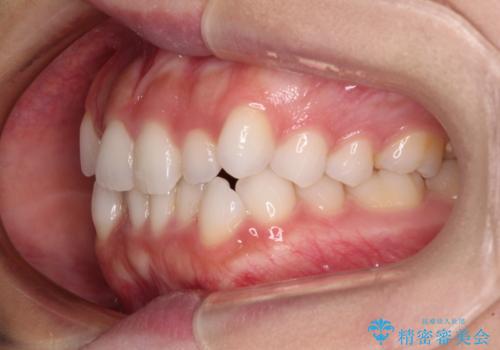

前歯のデコボコとクロスバイト ワイヤー装置での抜歯矯正

- 前歯のデコボコとクロスバイトを気にして来院された患者様です。

上下ともにデコボコはそれほど強くありませんでしたが、非抜歯では口元が突出した仕上がりとなる可能性があるため、上下左右の第一小臼歯4本を抜歯し、ワイヤー装置での抜歯矯正を行うこととしました

スペースを閉じるために期間を要しましたが、無事に綺麗な口元に仕上げることができました。